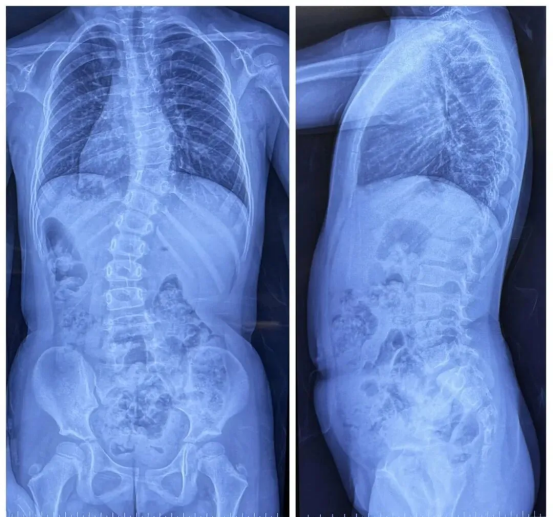

Patient: Female, 5 years old

Clinical Symptoms: Asymmetrical back, uneven shoulders, scoliosis

Surgical Indication: Congenital hemivertebra deformity accompanied by scoliosis, which affects normal growth and development. Surgical correction was necessary. Early surgical intervention can effectively prevent deformity progression and improve prognosis.

Surgical Approach: Posterior hemivertebrectomy combined with short-segment fixation and fusion

Surgical Goals: Eliminate the deforming element, correct spinal deformity, restore spinal balance, and preserve the patient's growth potential.

Preoperative imaging of the pediatric patient